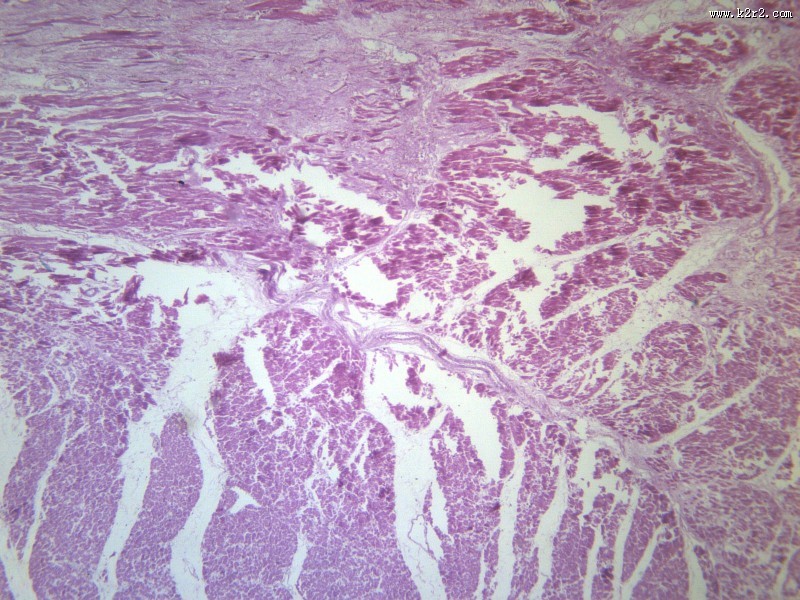

心肌梗死 - 第4张

心肌梗死

图集中 / 共有 12 张图片

风湿性心肌炎

显微切片

myocardial infarction